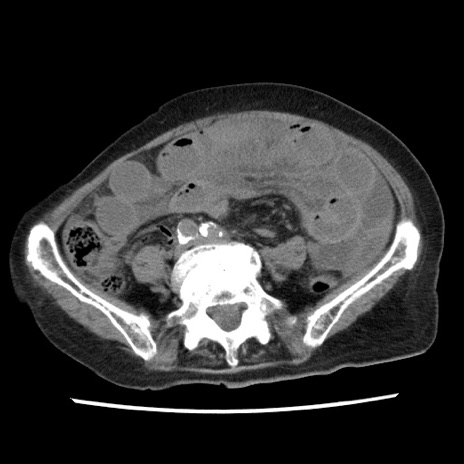

矢状断像

【症例】80歳代女性

【主訴】腹痛

【現病歴】8時間前から腹痛あり来院。

【既往歴】糖尿病、脂質異常症、子宮体癌にて子宮全摘術

【身体所見】意識清明・会話良好だが腹痛で苦悶様、全腹部にわたって反跳痛と圧痛あり

【データ】WBC 13600、CRP 0.14、LDH 224、CK 90